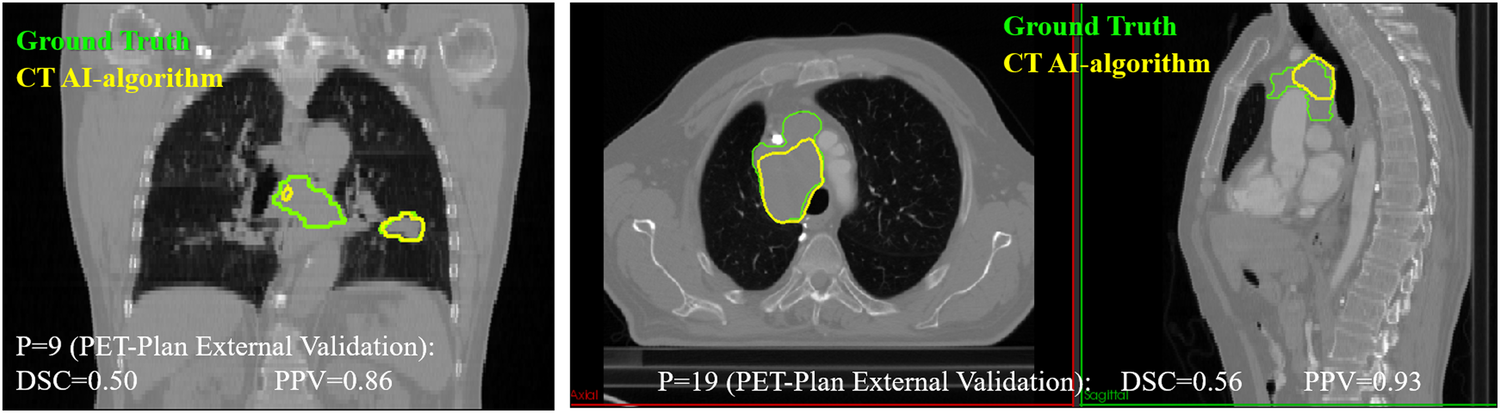

First, the model was tested with the 8 3D-CT images of patients retrospectively recruited. DSC(3D-CT) was 0.63 ± 0.34, improving 15% with respect to the experts DSC(3D-Expert) = 0.55 ± 0.11. The nnU-Net model showed an accuracy higher than 0.69, for all patients apart from two. The two DSC values for these two patients (0.12 and 0) are responsible of the difference between the average value (0.63 box cross in Fig. 5) and the median value (0.81, box line in Fig. 5). Second, the model was tested with the 19 3D-CT images of patients prospectively recruited in 9 different centres involved in the PET-Plan trial. DSC(3D-CT) was 0.59 ± 0.24. Overall, a trend of good detection but an underestimation of the size of the lesion was observed. This trend was confirmed by an average value of positive-predictive-value of 0.77 ± 0.23. In Fig. 6 examples of contours for two patients are shown, being DSC and PPV values also provided.

Fig. 6

Different CT segmentation approaches for two PET-Plan patients involved in the external validation